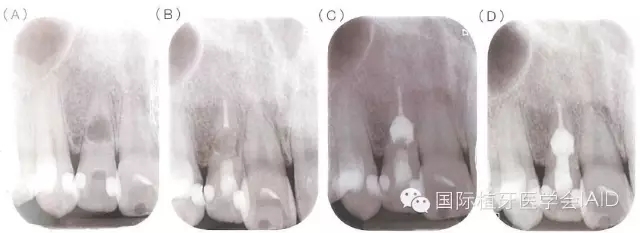

牙根內(nèi)吸收若是早期發(fā)現(xiàn),在未與牙周組織相通的情況下治療步驟相對(duì)單純以徹底去除導(dǎo)致牙髓腔內(nèi)感染與內(nèi)吸收窩洞內(nèi)的肉芽組織為首要目標(biāo),可運(yùn)用機(jī)械性的清創(chuàng)配合次氯酸鈉溶液與超聲波器械的沖洗,加強(qiáng)清創(chuàng)效果,之后于根管內(nèi)放置氫氧化鈣至少1~2周,在無臨床癥狀下,便能以古塔膠熱塑性封填系統(tǒng)(warmgutta percha technique)或是三氧礦化物(MTA,mineral trioxide aggregate)進(jìn)行根管封填;但若此內(nèi)吸收為與外界相通的牙根吸收病灶,由于MTA具有良好的密封能力(sealingability)及生物兼容性(biocompatibility)會(huì)是更恰當(dāng)?shù)倪x擇(下圖)。

(A)31歲男性因牙位12顏色改變求診,該牙無臨床癥狀,但X光檢查發(fā)現(xiàn)在牙根中段有一個(gè)約4.5*5mm的橢圓形呈放射線透性影像,檢查時(shí)牙髓組織已無活性反應(yīng)并診斷為牙根內(nèi)吸收。(B)于顯微鏡下進(jìn)行根管治療,根管內(nèi)有出血現(xiàn)象且有肉芽組織沾粘于管壁,懷疑病灶與根管外相通,移除發(fā)炎組織后進(jìn)行根管清創(chuàng)搭配超音波器械沖洗,并放置氫氧化鈣。根管封填分兩部份進(jìn)行,先以古塔膠填充填下半部根管;(C)以MTA充填于吸收窩洞,確認(rèn)MTA硬化后,以復(fù)合樹脂填補(bǔ)根管開口;(D)根管治療完成后一年的追蹤,該牙無癥狀且周邊組織愈合良好。